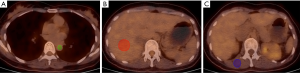

Background mean SUVs from the ABP, liver, and muscle were recorded. ABP activity was calculated by drawing three circular regions of interest (ROI) on three contiguous slices within the lumen of the thoracic aorta, taking care not to include the vessel wall in the ROI (Figure 1A). The liver 18F-FDG SUV was determined manually by placing an ROI with a diameter of 3 cm by 2 cm volume in the right hepatic lobe at the level of the main portal vein (Figure 1B). The muscle SUV was determined by selecting an ROI in the erector spine at the level of the 12th thoracic vertebra, including three contiguous slices within the margin of the muscle (Figure 1C). All operations were conducted by the post-processing software of the PET/CT viewer (Philips, Netherlands). SUVs were then normalized for lean body mass (LBM) using the following formulas (10,11):